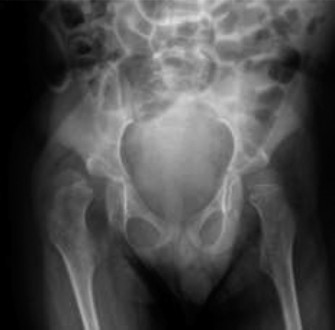

CASE 37 A 4-year-old male with cerebral palsy is brought to your clinic for eva…